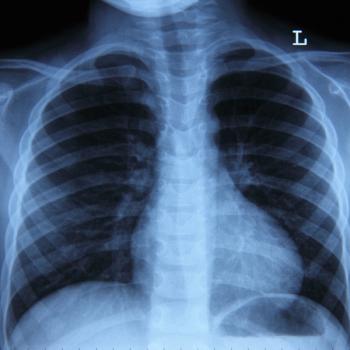

Camrelizumab combo doubled the five-year survival rate in advanced squamous lung cancer, reducing mortality risk by 43%, in a Phase 3 trial.

Tagrisso is associated with positive outcomes among patients with unresectable stage 3 EGFR-mutant non-small cell lung cancer.

The COCOON trial regimen reduced dermatologic side effects in patients with EGFR-mutant non-small cell lung cancer, phase 2 trial data showed.

First-line Rybrevant plus Lazcluze significantly extended overall survival versus Tagrisso in mutated, advanced or metastatic non-small cell lung cancer.